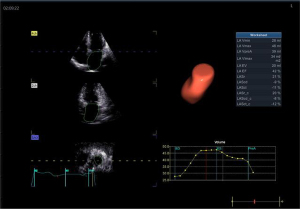

Image acquisition and data analysis of RT-3D Auto LAQ

RT-3D Auto LAQ image acquisition operation guidelines: (I) use the 4Vc matrix probe was to obtain two-dimensional images at the standard four-chamber heart section, and adjust the sector depth and gain to make the left atrium clearly visible in all the apex views; (II) Breath-hold at end-expiration; acquire 4–6 cardiac-cycle four-dimensional (4D) full-volume loops; (III) transfer to EchoPAC; select the best loop, open 4D Auto LAQ; (IV) at end-systole, place the sampling point at the mid-mitral annulus in each apical plane; align axes; (V) activate the “review” interface to check whether the LA endocardium curve automatically outlined by the system is consistent with the real endocardium. If there is any deviation, manually drag and drop the sampling line to make it coincide with the endocardium while excluding the pulmonary vein inlet and LA auricle area, then click “result” for LA volumes and strain, as shown in Figures 1-4. The LA volume parameters are divided by the body surface area (BSA) of each case to obtain the corresponding volume indices. Further calculations are performed to determine the left atrial total emptying fraction (LATEF) = (LAVmax-LAVmin)/LAVmax; left atrial passive emptying fraction (LAPEF) = (LAVmax-LAVpreA)/LAVmax; left atrial active emptying fraction (LAAEF) = (LAVpreA-LAVmin)/LAVpreA; and left atrial expansion index (LAEI) = (LAVmax-LAVmin)/LAVmin. The LA function parameters include the left atrial storage period strain (LASr), the left atrial conduit period strain (LAScd), the left atrial systolic period strain (LASct), and the corresponding left atrial storage period circumferential strain (LASr-c), left atrial ductile period circumferential strain (LAScd-c), and left atrial systolic period circumferential strain (LASct-c) (16). Among them, LAEI, LASr, and LASr-c represent the storage function of the left atrium; LAPEF, LAScd, and LAScd-c represent the function of the LA duct; and LAAEF, LASct, and LASct-c represent the active contraction pump function of the left atrium. All parameters were averaged twice.